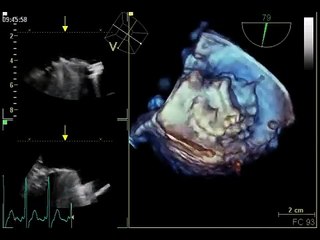

Repairing a leaky mitral valve in heart